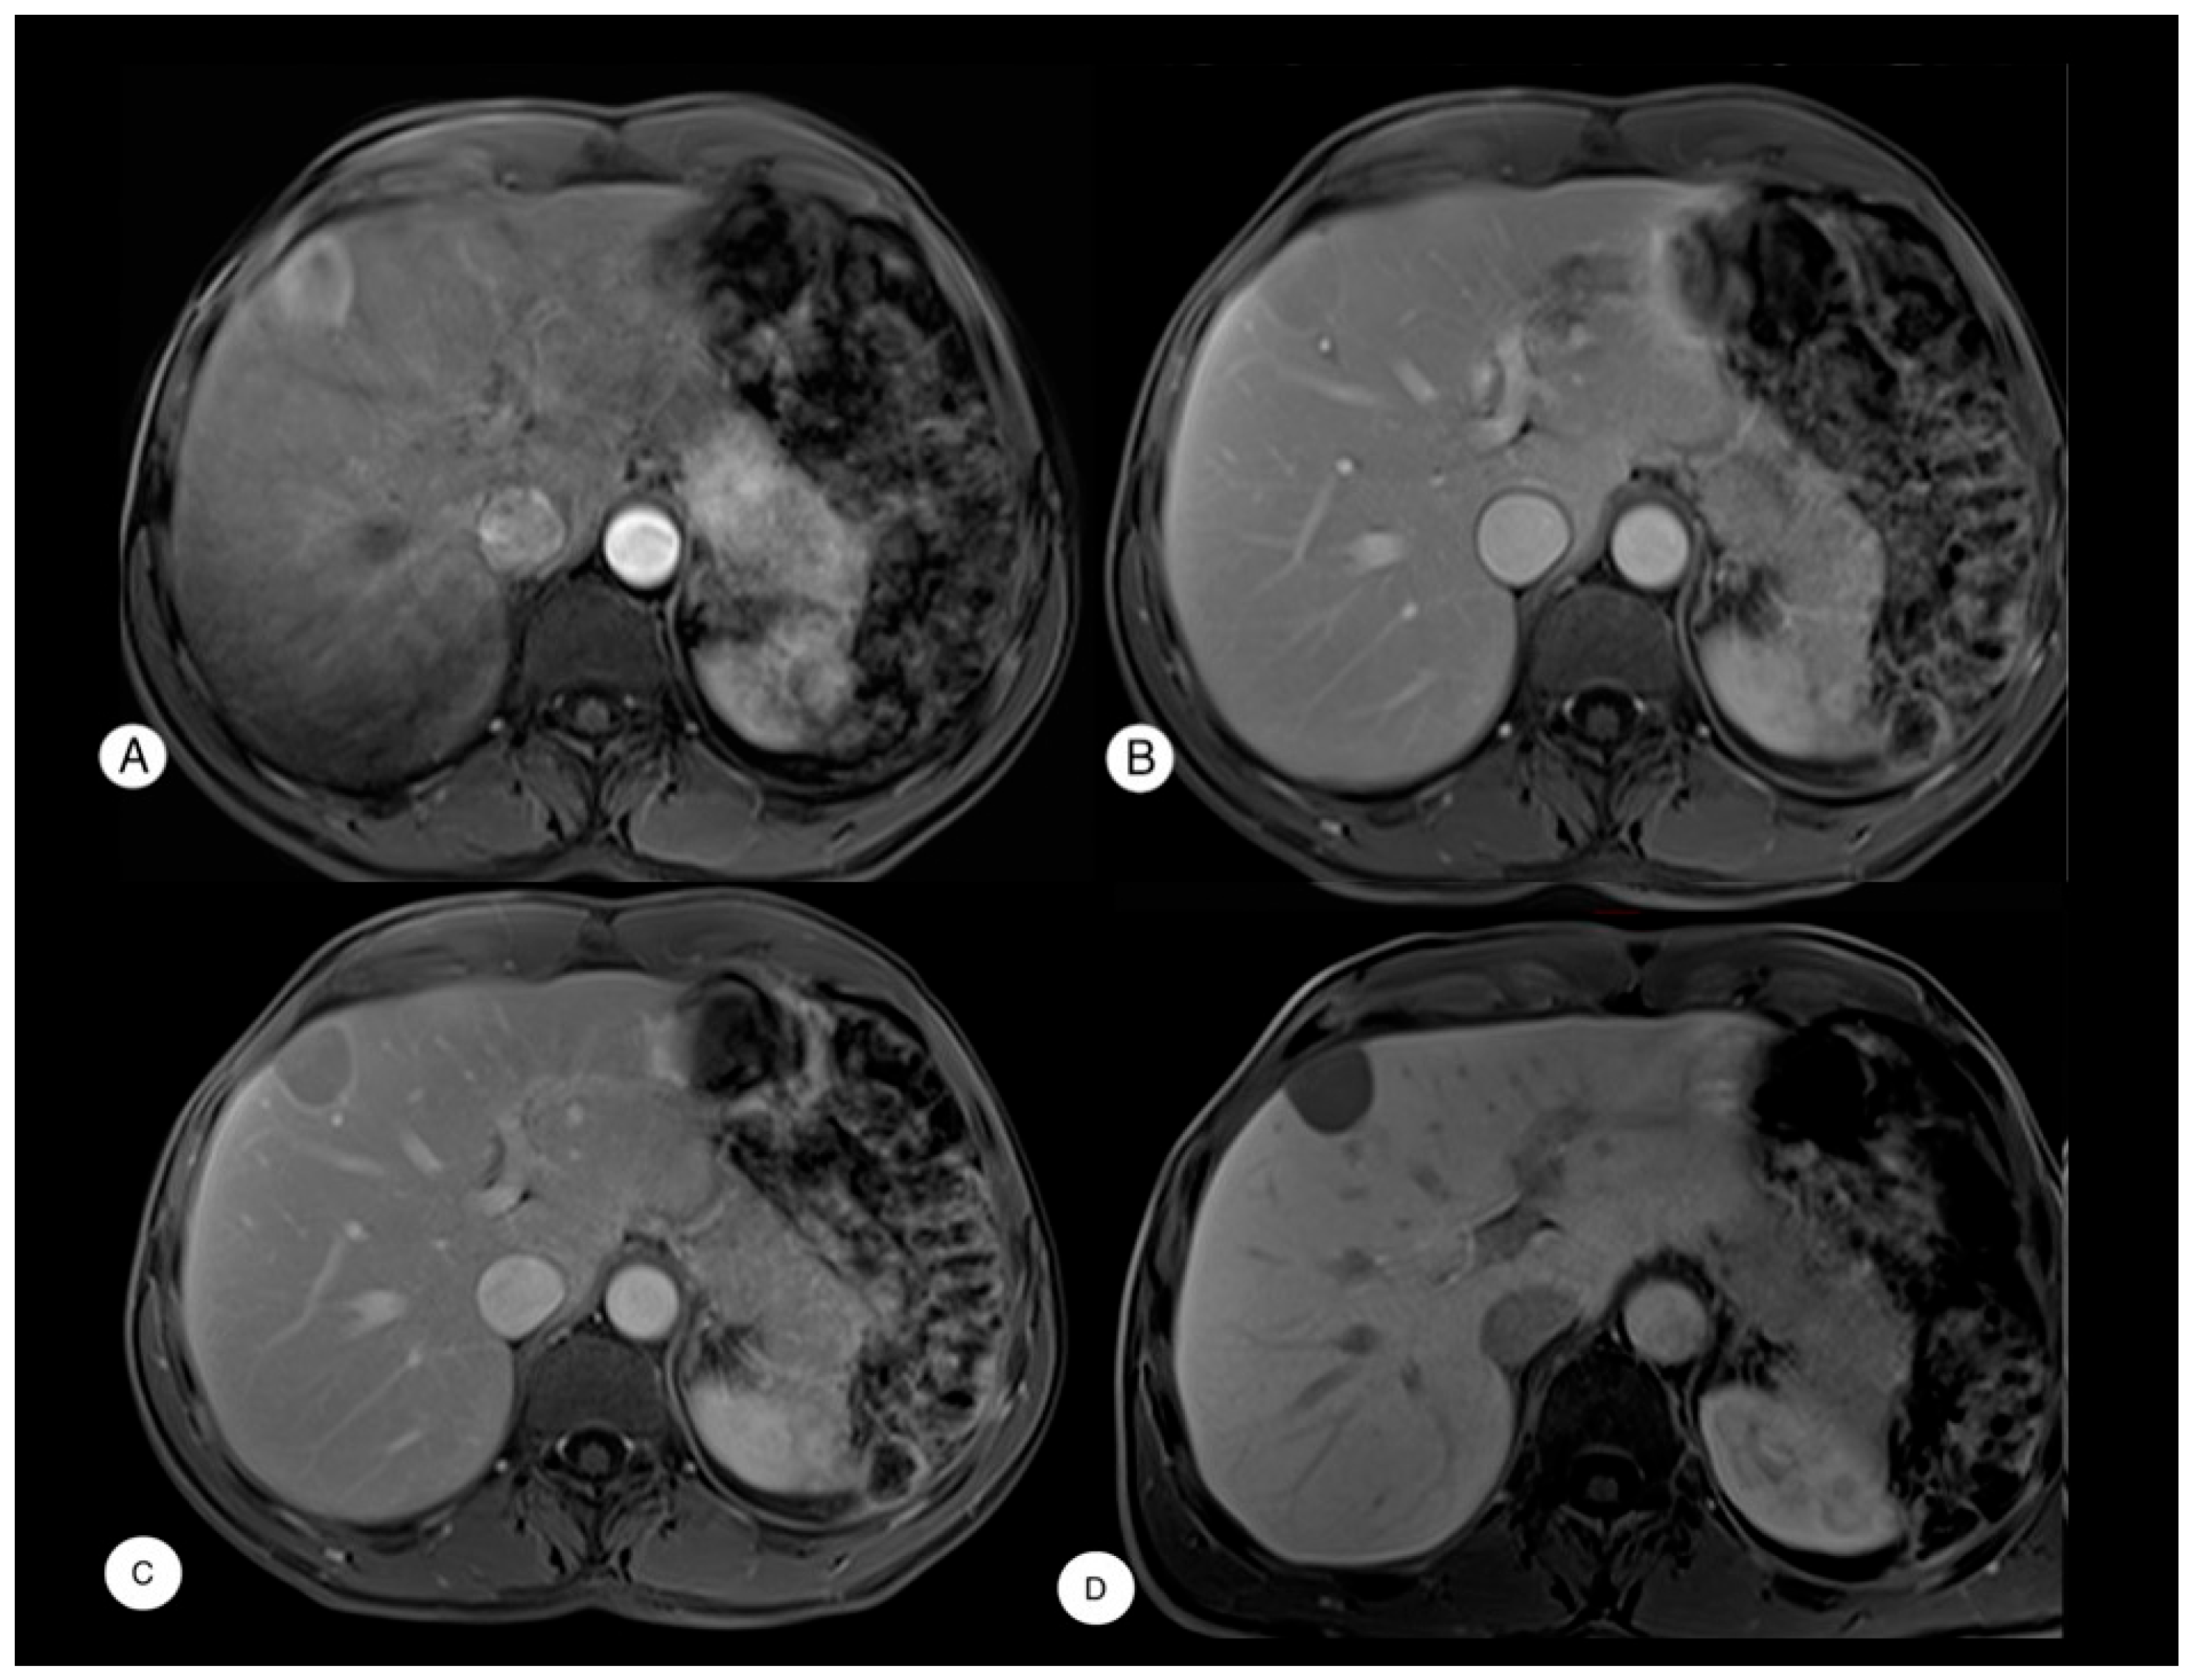

Case Presentation